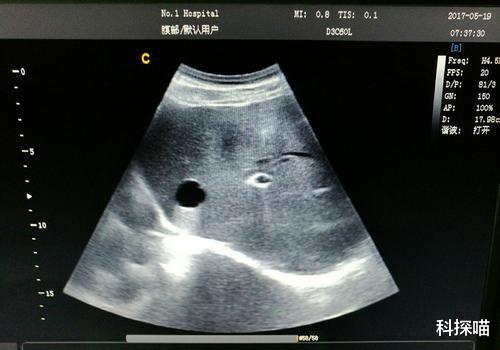

2、肝囊肿

肝囊肿是比较常见的肝脏疾病 , 很多人在听到囊肿时会认为是可怕的肿瘤 , 都认为要治疗或者进行手术切除 , 却不知有些肝囊肿不需要理会 , 只需要定期检查即可 。

但如果发现肝囊肿直径超过5厘米或者有明显症状 , 如腹痛、上腹不适等 , 就需要及时采取相对应治疗措施 。 在目前肝囊肿最佳治疗方法是进行手术治疗 , 不仅安全 , 创伤性也比较小 。